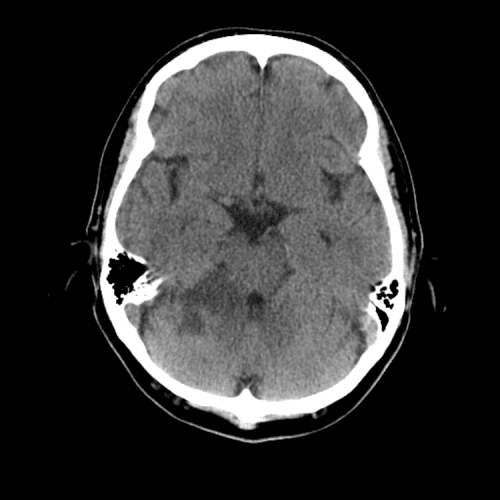

PCA infarct